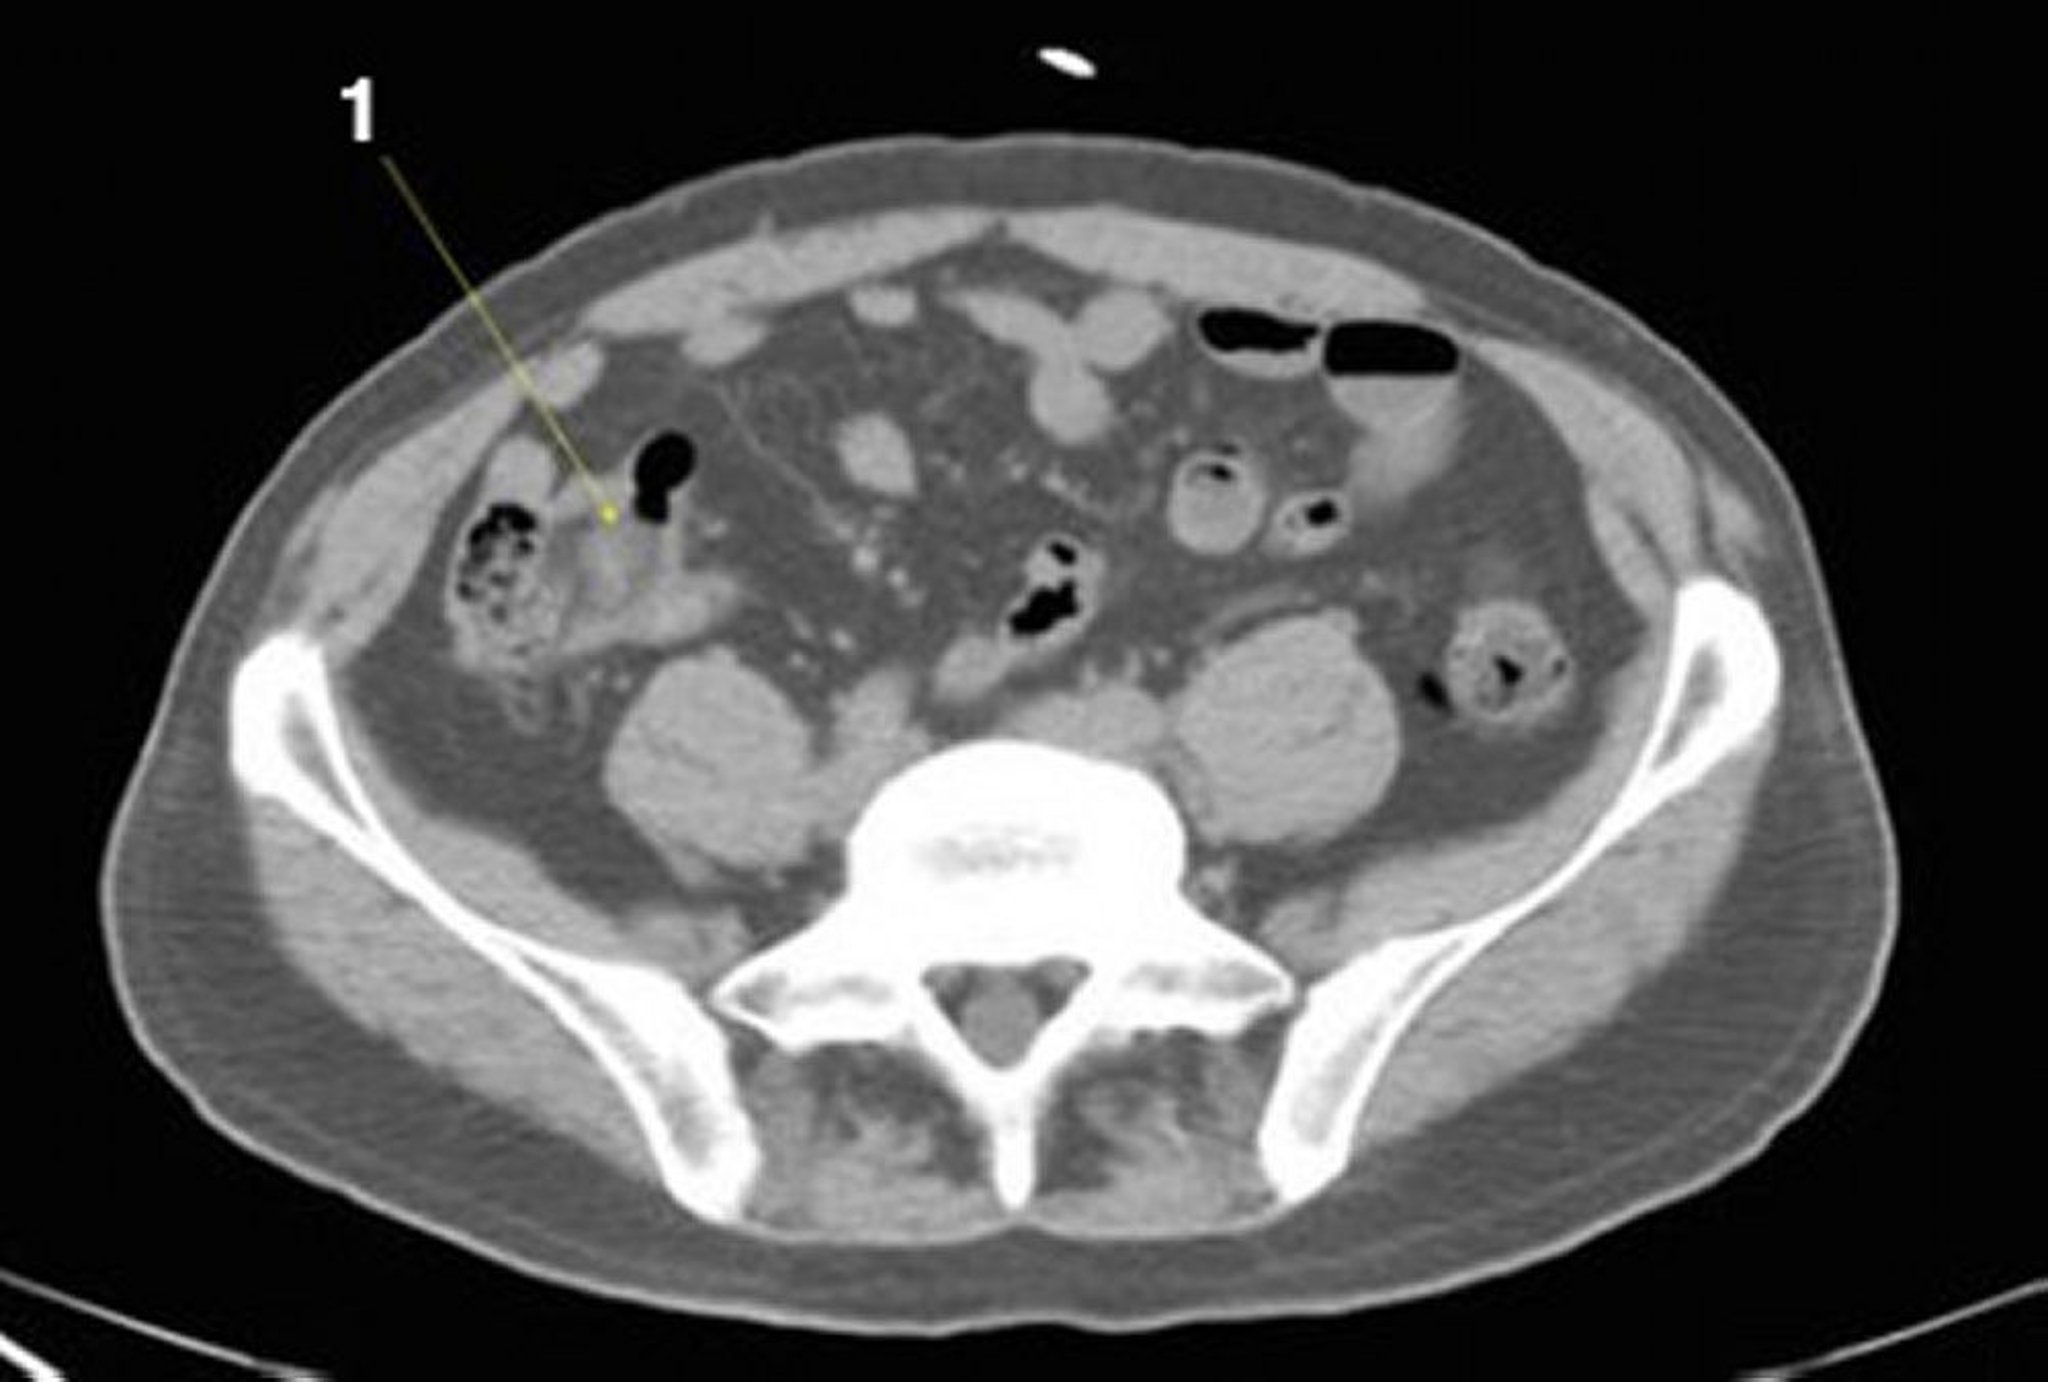

Tomografía computarizada sin contraste de abdomen y pelvis que muestra anatomía normal (corte 21)

1 = íleon.